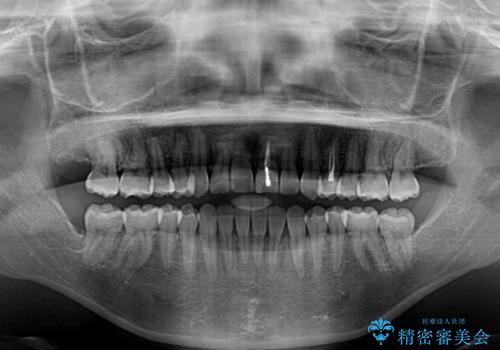

前歯のクロスバイトと変色した歯 ワイヤー矯正とセラミック治療

- 前歯のクロスバイトと神経を取り除いた後に変色してしまった前歯を気にして来院された患者様です。

ワイヤー矯正により矯正治療を行った後に、前歯の補綴治療を行うこととしました。

変色してしまった前歯は、反対側の歯と比べて歯肉が覆い被さっていたため、骨整形を含めた歯周外科処置を行い、歯肉ラインを整えることとしました。